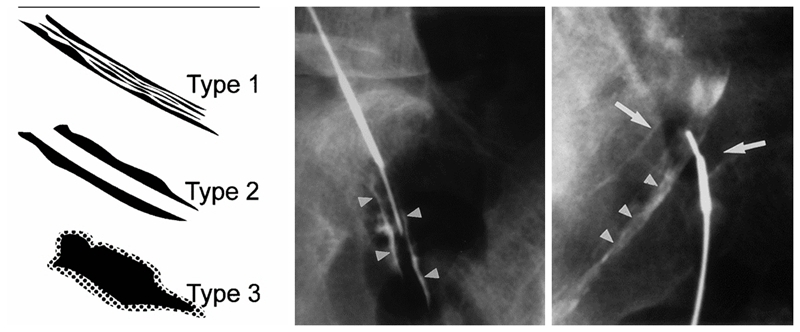

图3

RN入路注射又可分为两种方式,即神经根鞘膜内注射(intra-epineuralinjection)和神经根周围注射(intra-epineuralinjection)。通过造影剂注射可以区分这两种不同的方法,当针尖进入神经根鞘膜内时,会获得神经根内羽毛状神经纤维的显影,而针尖在神经根周围时,造影剂会显示神经根的轮廓。